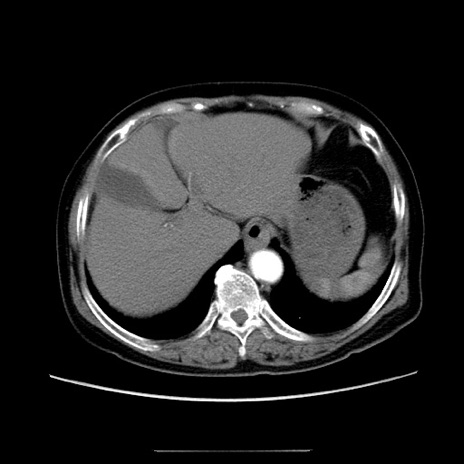

症例5(横断像)

【症例】70歳代女性

【主訴】お腹が張る

【現病歴】1週間くらい前から腹部膨満の自覚あり。昨日夜から増悪したため、本日救急外来受診。

【身体所見】意識清明、BT 36.5℃、BP 165/106mmHg、HR 80bpm、SpO2 98%、腹部:膨満、軟、自発痛・圧痛なし、触診にて不快感あり、腸蠕動音:減弱

【データ】WBC 12600、CRP 1.04